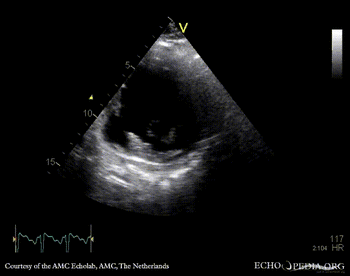

Free wall rupture of left ventricle

E00829.gif E00830.gif

Subcostal view: septal rupture PSAX: septal rupture